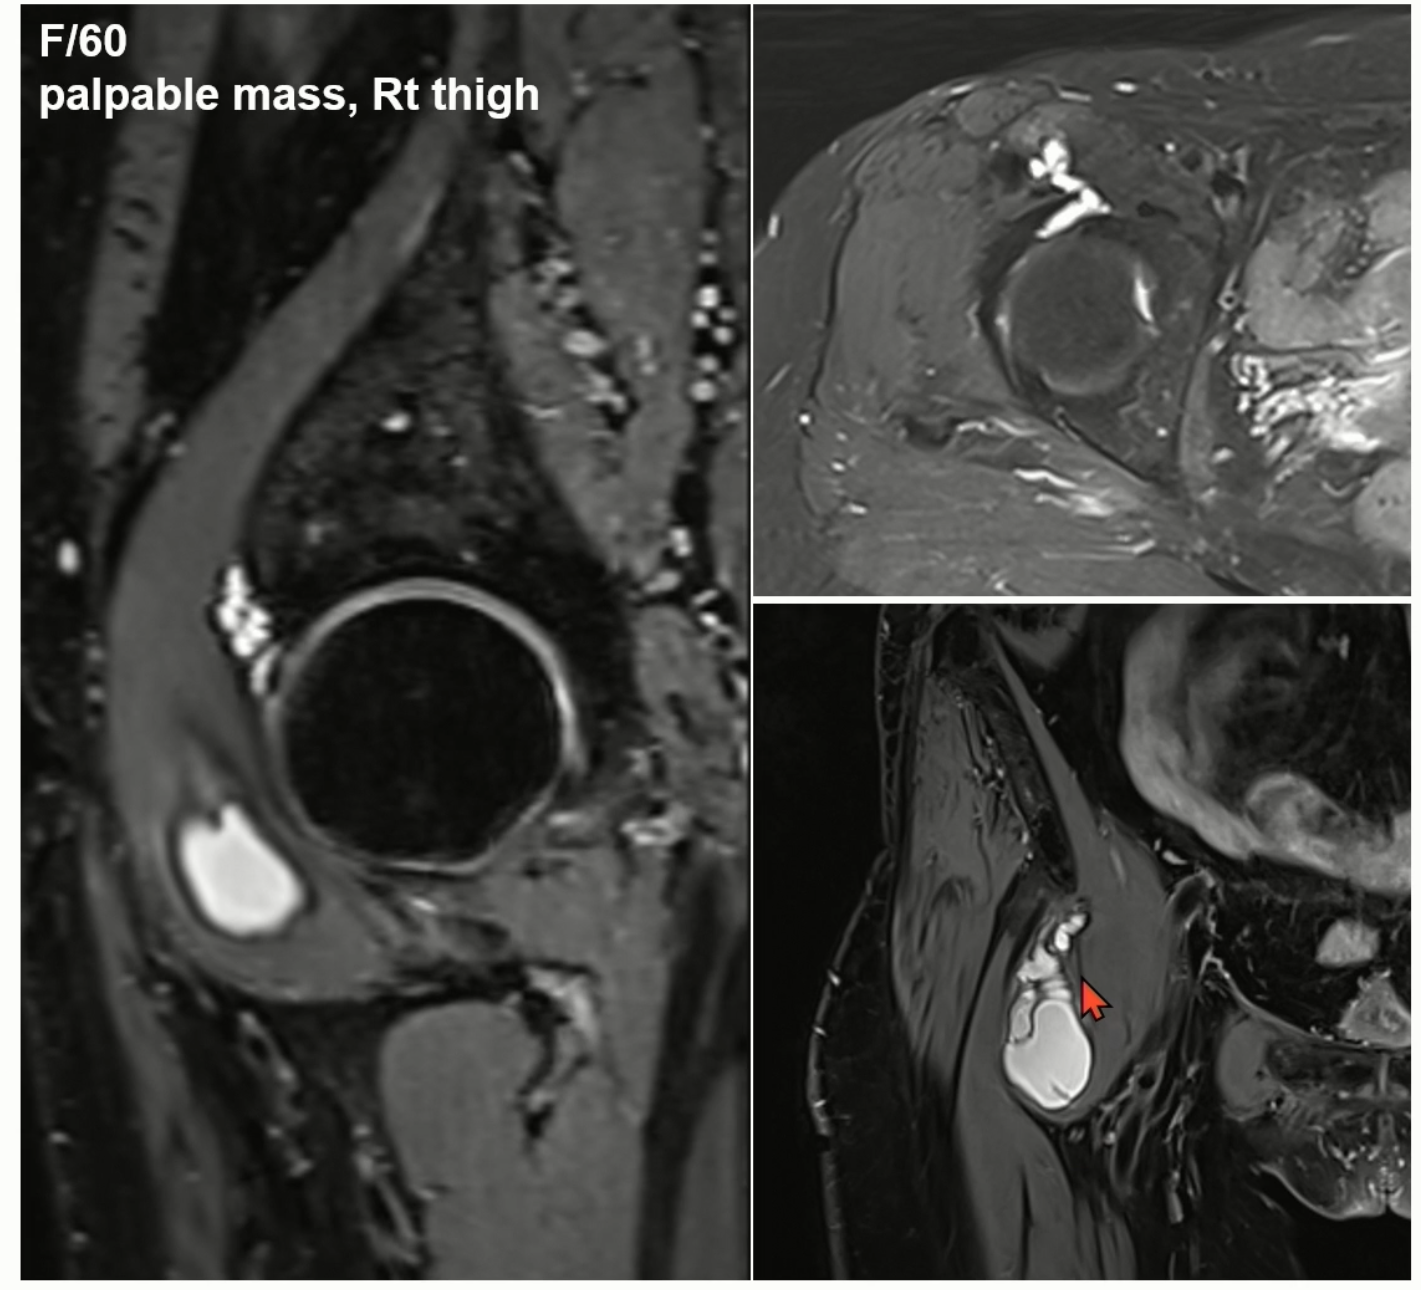

Case 3)

antero-superior Labral tear에 Paralabral cyst가 동반된 상태